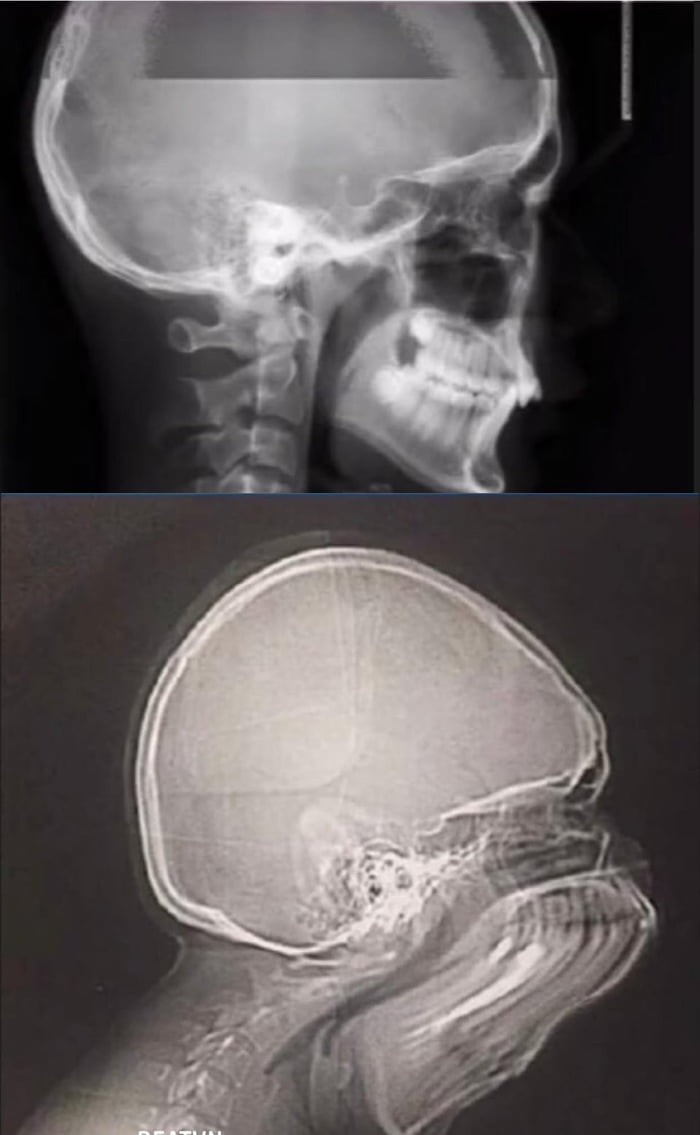

Вот что произойдет, если вы чихнете во время рентгена